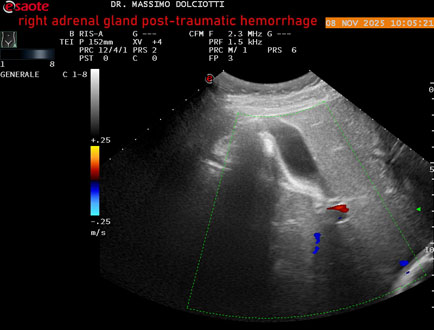

Data inserimento: 10/11/2025

Ecografia del: 08/11/2025

Strumento: Esaote MyLab Eight

Sonda: Convex Multifrequenza 1-8 MHz

Età Paziente: M 49 anni

Motivazione dell'esame: follow up per emorragia al surrene destro post-traumatica (incidente stradale).

Commento all'esame: le immagini ed il video documentano in sede surrenalica destra, formazione ipo-anecogena, a margini definiti, ovalare, delle dimensioni di 38,6 x 19,7 mm, da ricondurre ad emorragia post-traumatica.

Conclusioni: emorragia post-traumatica al surrene destro (post-traumatic hemorrhage to the right adrenal gland).

Presentazione: Dr. Massimo Dolciotti - Ancona